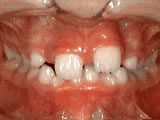

Overjet - Protruding front teeth

overjet beforeBefore

overjet afterAfter

At age ten, patient had a big overjet with the top teeth protruding beyond the bottom. She had two phases of treatment. The first helped her jaws to grow more harmoniously and the second aligned her teeth and bite. At age 13, she was proudly displaying her new smile.